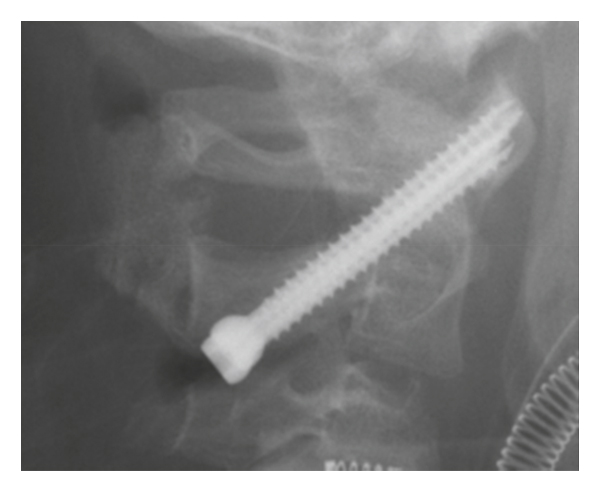

We performed C1-C2 Magerl surgery without bone fusion as a temporary fixation (Figures 2(a) and 2(b)) because the patient was 6 years old and we expected C1-C2 motion preservation after the removal of the screws [10]. We chose the Magerl technique instead of C1 lateral mass screw-C2 pedicle screw and rod fixation because there was abnormal hypervascularity posterior to C1 on preoperative 3D CT angiogram (Figure 2(e)). A plain radiograph and CT image after the surgery showed improvement of AARF, but the odontoid process appeared osteolytic (Figure 2(c)).

Considering bone union between C1 and C2, we removed the screws at 17 weeks after the surgery. However, the type 2 AARF recurred 2 weeks after the screw removal. Reconstructed CT images showed osteolysis of the odontoid process (Figure 2(d)). Just before the removal surgery, the WBC count was 10,800 and the CRP level was 0.0; inflammation of the transverse ligament and the influence of upper respiratory infection were suspected. Although we did not notice initially, retrospectively, osteolysis of the odontoid process was shown in the preoperative CT scan (Figure 1(c)).

We performed posterior fixation surgery using the Magerl–Brooks method with an iliac bone graft 5 weeks after the recurrence (Figure 3) [10, 11]. Ultimately, bone union was achieved 11 months after the surgery, and the screws were removed because we were concerned about growth disorder of the cervical bone without removal. On the most recent CT images, the odontoid process showed sclerosis and there were no signs of inflammation of the transverse ligament.